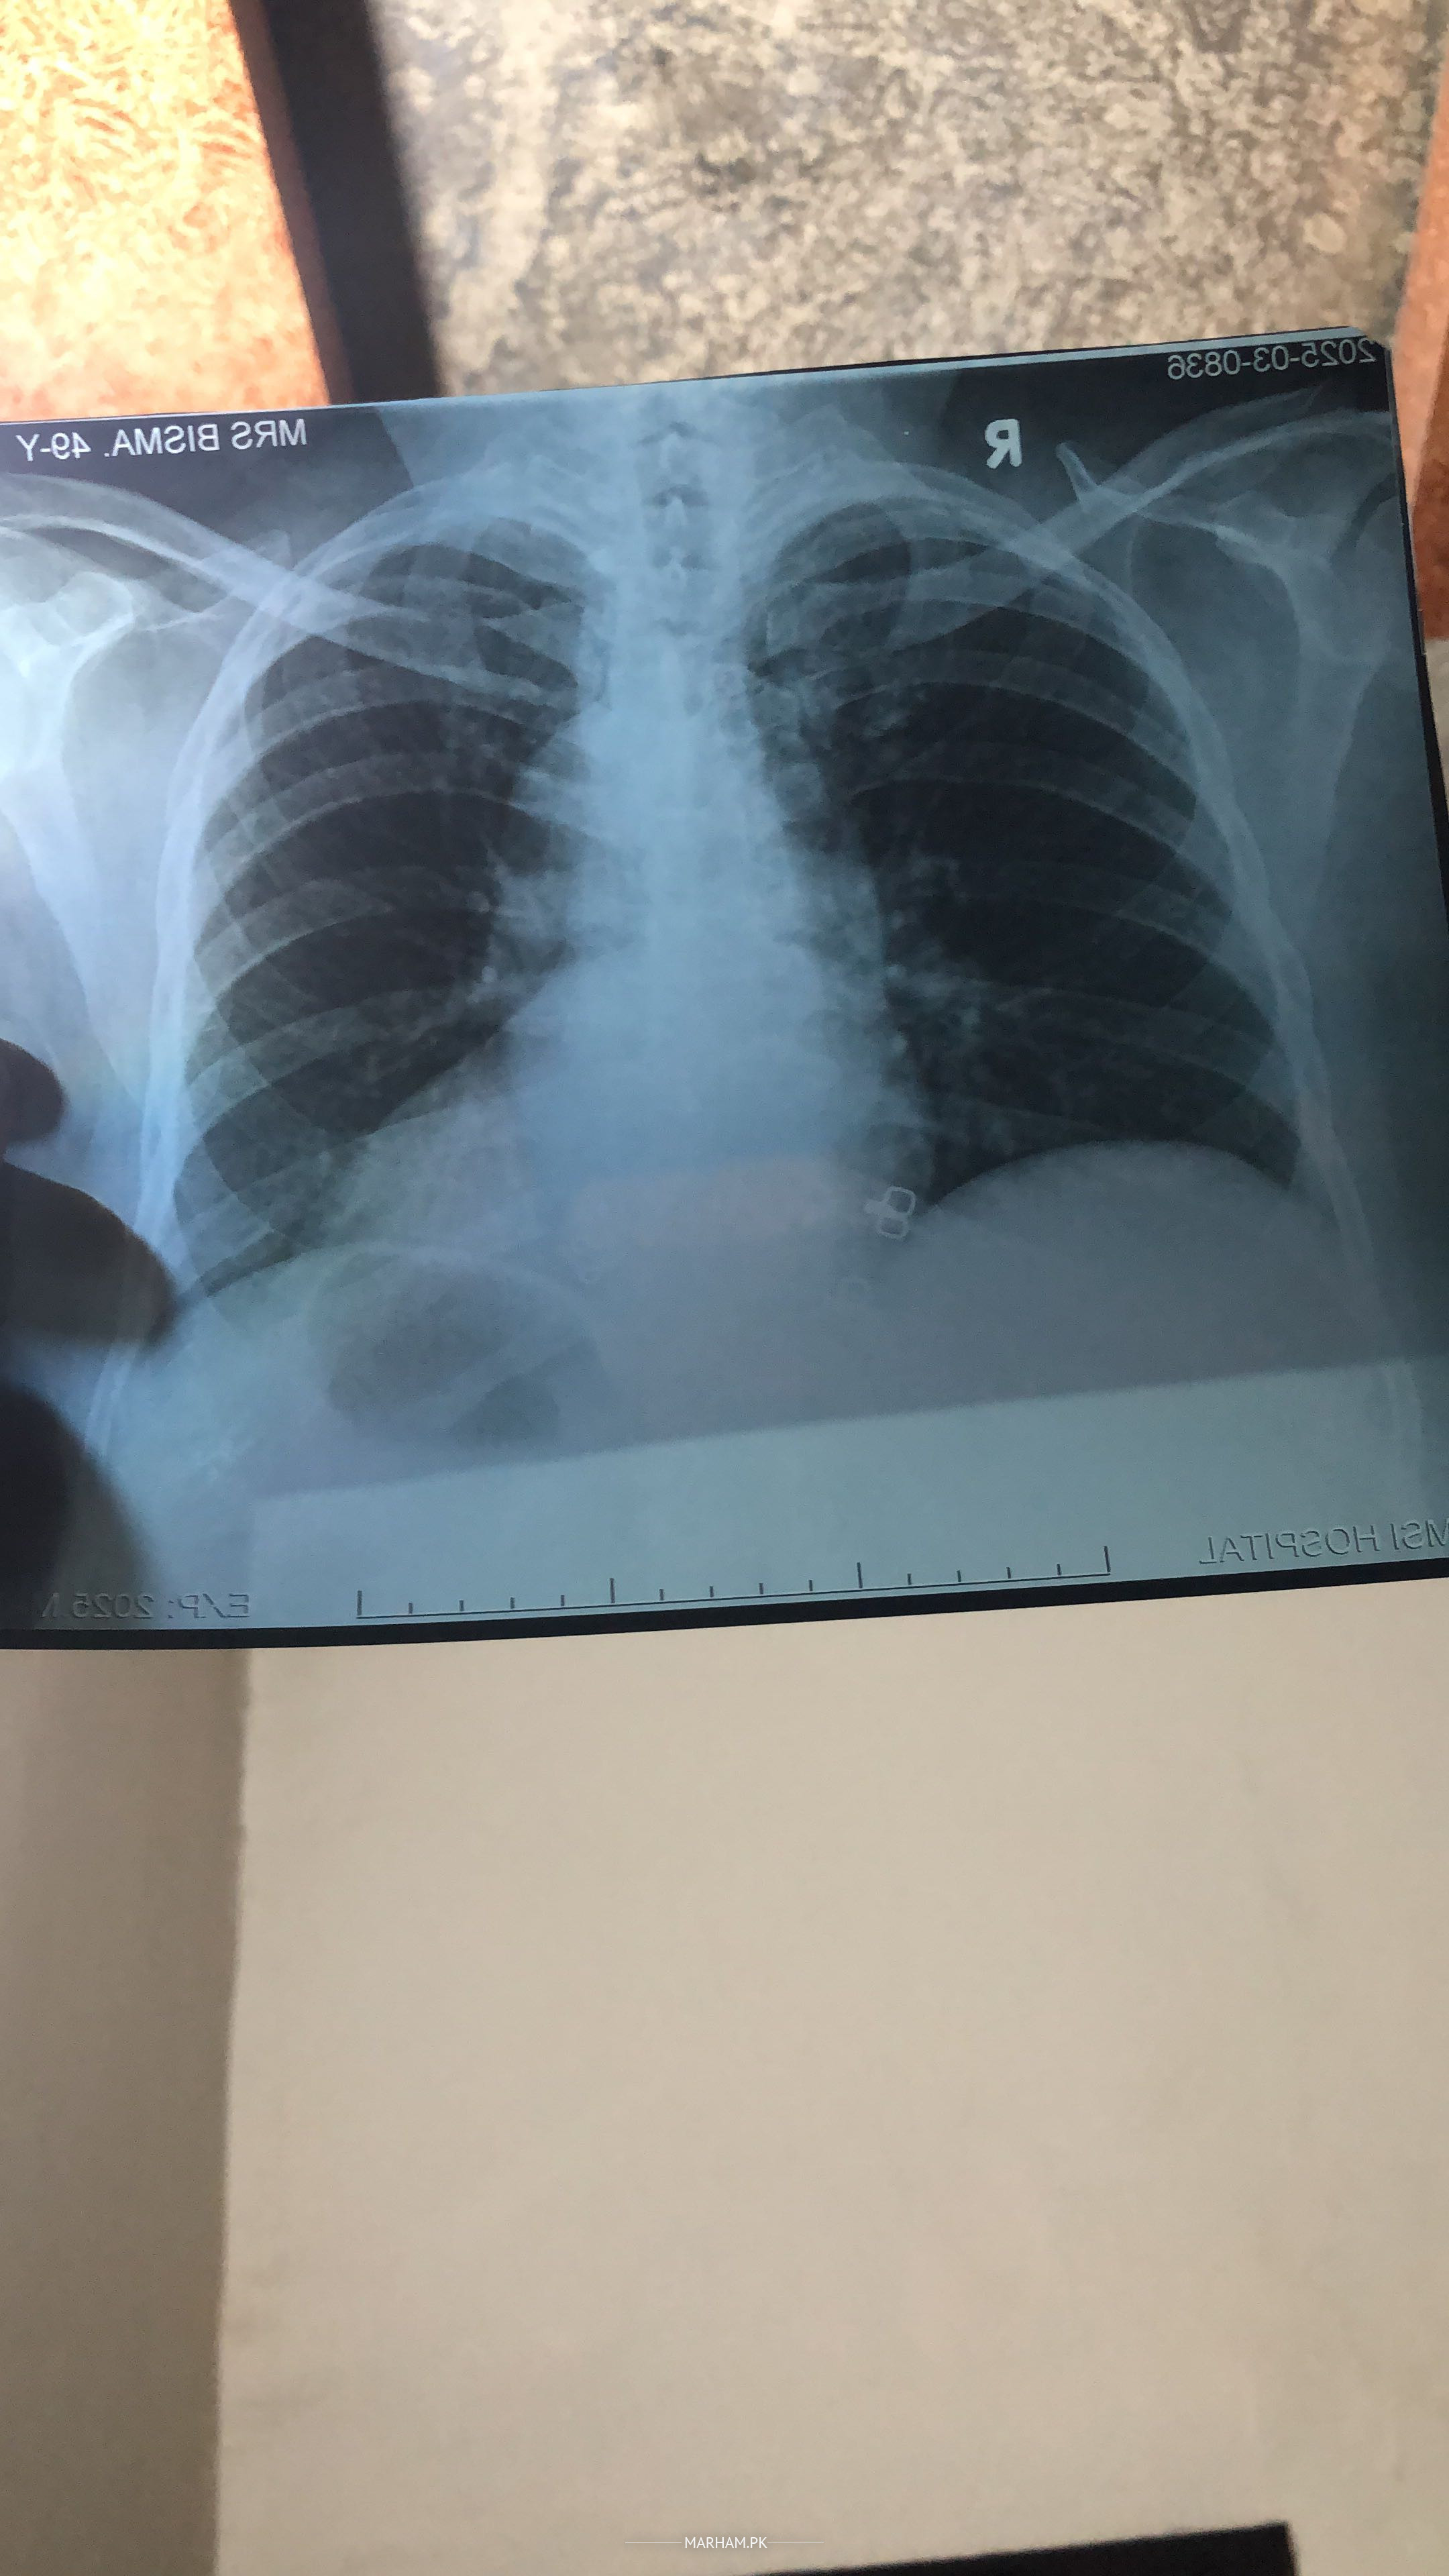

Kia plz baata skty hain k Chest Clear hai ya Infection hai?

seems to be clear....book an online video consultation

History is always needed with investigations.

hello. there seems to be a minor amount of fluid in the left side of her lung. i need to know the symptoms in order to prescribe medication. please contact me on whatsapp to know about the complains.

thanks

It’s normal CXr

Attach Photo here: